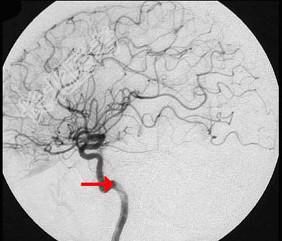

单项选择题如图箭头所示是大脑哪根动脉 ( )

A、大脑中动脉

B、大脑后动脉

C、基底动脉

D、颈总动脉

E、颈内动脉